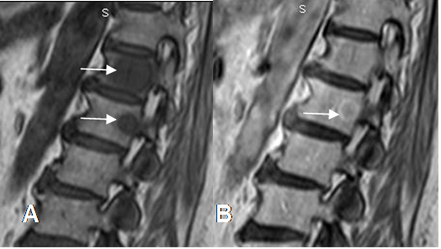

Fig 31. Tumor metastásico.

A: RM sagital en T1. Lesiones hipointensas en D12 y L1, por enfermedad metastásica de próstata.

B: RM sagital en T1 con contraste. Realce con halo hiperintenso, signo de enfermedad metastásica.